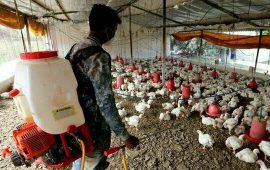

È stato rilevato il primo caso di infezione umana del ceppo H10N3 dell’influenza aviaria in Cina. Il caso è stato registrato nella città di Zhenjiang nella provincia dello Jiangsu – a renderlo noto la Commissione Nazionale della Sanità del Paese